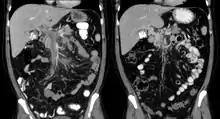

Portal vein thrombosis seen with computed tomography.

Portal vein thrombosis on computed tomography (left) and cavernous transformation of the portal vein after 1 year (right)